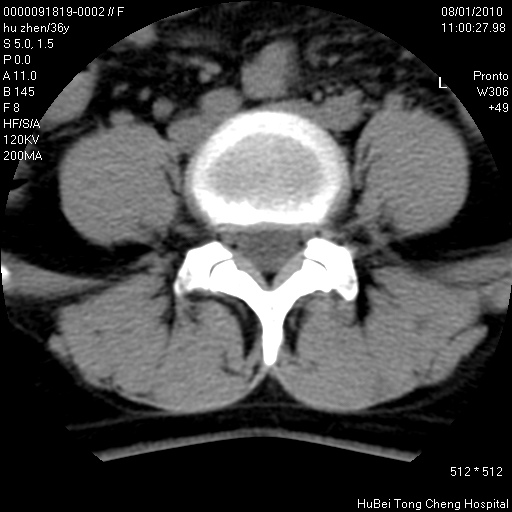

患者 女,36岁。右侧腰腿痛半月余。腰骶椎mr平扫偶然发现骶椎异常信号。

临床诊断:1)腰椎间盘突出症。2)骶椎肿瘤性病变?

骶椎ct平扫(层厚、层距均为5mm),图像如下:

考虑s1骨纤维异常增殖症。